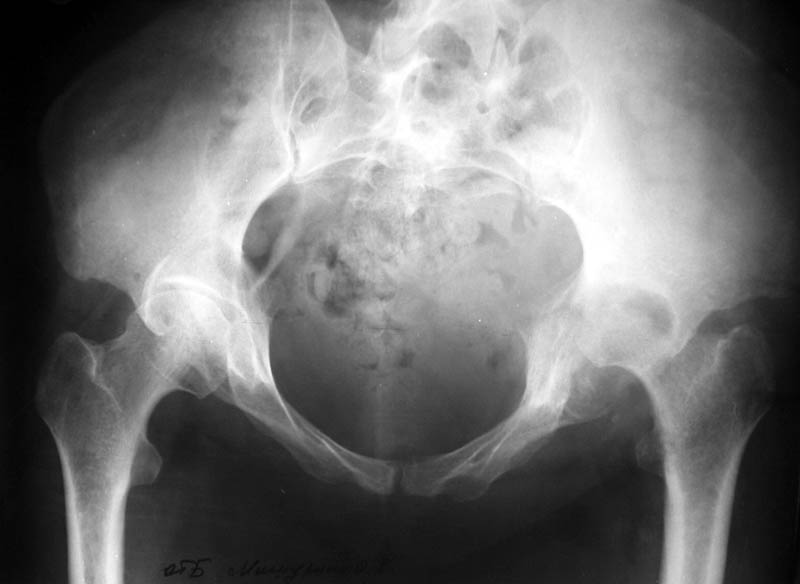

Женщина, 45 лет. В марте перенесла левосторонний коксит неизвестной этиологии. Специфику и онкологию исключили.

Интраартикулярных инъекций не было. Сейчас процесс клинически и рентгенологически - стабилизировался. Состояние вполне удовлетворительное.Предполагается тотальное эндопротезирование с пластикой полости аутокостью. Возможна ли бесцементная <чашка>? Заранее благодарю! С уважением,А.В.Владзимирский

Пртезирование через пол года после коксита закончившегося лизисом сустава, который на снимках выглядит как гнойный? Что значит неизвестной этиологии?

Уважаемый коллега! Последняя версия - мы пролистали ренгенологическую книженцию-так картинка вполне подходит под сустав Шарко (neuropatic joint ). В тазобедренном суставе патология редкая (но меткая). Ищите причину - варианты - нейросифилис, сирингомиелия, опухи спинного мозга (и выше тоже) компрессия спинного

мозга извне, рассеяный склероз, алкоголизм. А так-же : склеродерма ,Рейно,ревматоидный артрит, амилоидная инфильтрация нервов,и это не считая всяких менингеомиелоцеле,asymbolia,Riley-Day syndrom,и все возможные другие нейропатии. На данном этапе не спешите оперировать(протезирование протиопоказано при нейропатических суставах),проконсультируйтесь с классным невропатологом,сделайте МЯР головного озга и

весь позвоночник. И держите нас в курсе - случай крайне интересный :)